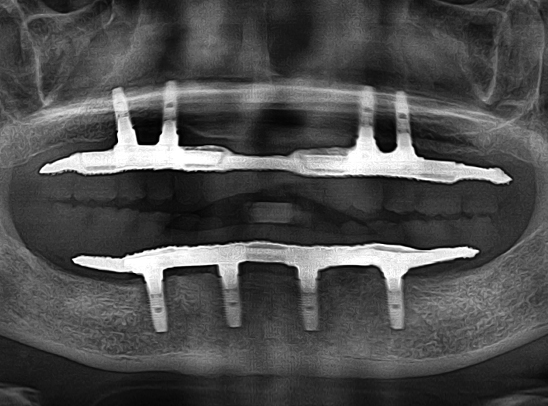

식립 개수를 줄이는

시니올 임플란트

식립 개수가 많은 과거의 임플란트

식립 개수를 줄인 시니올 임플란트

과거에는 대교 건설 시 기술이 부족해 교각을

촘촘히 세웠지만,

현대에서는 공법이 발달해

교각 수를 줄일 수 있게 되었습니다.

임플란트도 마찬가지 입니다.

컴퓨터 분석과 젊어지는치과의

22년의 전체 임플란트

노하우를 통해

식립 개수를 줄이면서도 완성도를

높일 수 있게 되었습니다.